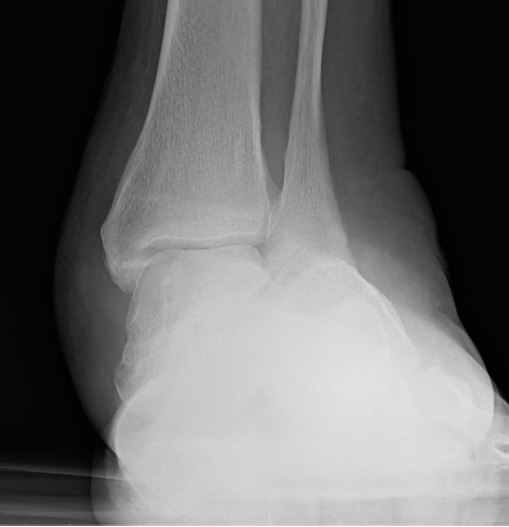

Hindfoot and Ankle surgery

Tibiocalcaneal (TCC) arthrodesis

DeVries et al J Foot Ankle Surg 2012

- 52 patients with Brodsky type 3a Charcot destruction of the ankle

- TCC arthrodesis

- 75% limb salvage rate

Caravaggi et al J Foot Ankle Surg 2012

- 45 patients treated with TCC arthrodesis with nail

- 4% had tibial fracture above the nail

Yammine et al J Orthop Surg 2019

- systematic review of TCC fusion in charcot hindfoot

- external fixation v IM nail

- IM nail double fusion rate and faster